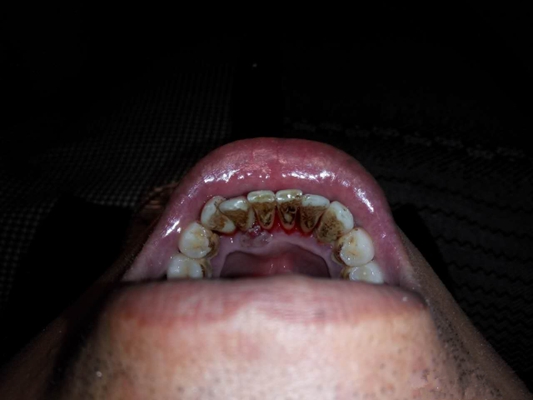

牙周炎圖片

牙周袋 (9)